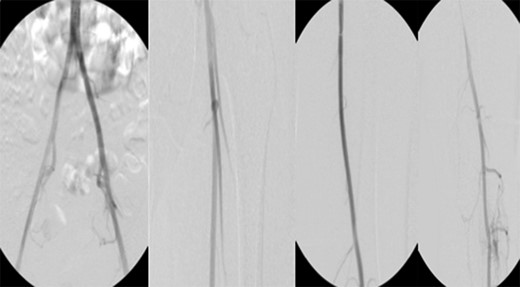

Patient underwent a left lower extremity angiogram. During the procedure she was found to have patent aorta and bilateral common iliac artery. There was no disease visualized in the left external iliac artery, common femoral artery (CFA), SFA, patent previously placed stent, patent above and below the knee PA and two vessel run off to the foot (Fig. 1). Upon delayed fluoroscopic images we identified contrast filling the deep venous system rather quickly suggesting a high volume fistula (Fig. 2). We then identified the fistula between ATA and ATV. Although ATA was previously ligated there was retrograde filling of the artery from unnamed branches, which communicated with the venous system as shown in. In the midcalf (ATA) was cannulated with a micropuncture needle. Micropuncture wire was inserted and a 5-Fr sheath was inserted after exchanging over wire. At this point VortX coils (Boston Scientific) were placed from the curve of ATA until the whole AVF was sealed. Anterograde angiogram showed no flow through the fistula (Figs 3 and 4). There was a palpable PT and DP pulse at the completion of the procedure. Sheath was removed, pressure dressing applied. Patient was discharged home same day. Recovery has been unremarkable. Three months follow-up claudication symptoms have significantly improved.

Fluoroscopy imaging showing high volume anterior tibial artery to vein iatrogenic fistula.